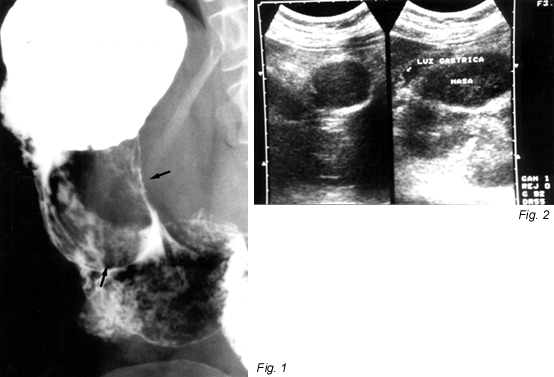

| leiomyoma | term type: main entry term part of speech: noun number: singular reliability code: 9 definition: benign myoma that develops in the smooth muscle tissue. (en) context (x): i_leimyo.txt origination date: 04/06/2002 |